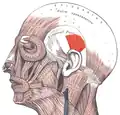

Face and neck muscles. Superior auricular muscle shown in red. | |

The muscles of the auricula. Superior auricular is at top (indicated by the red arrow). | |